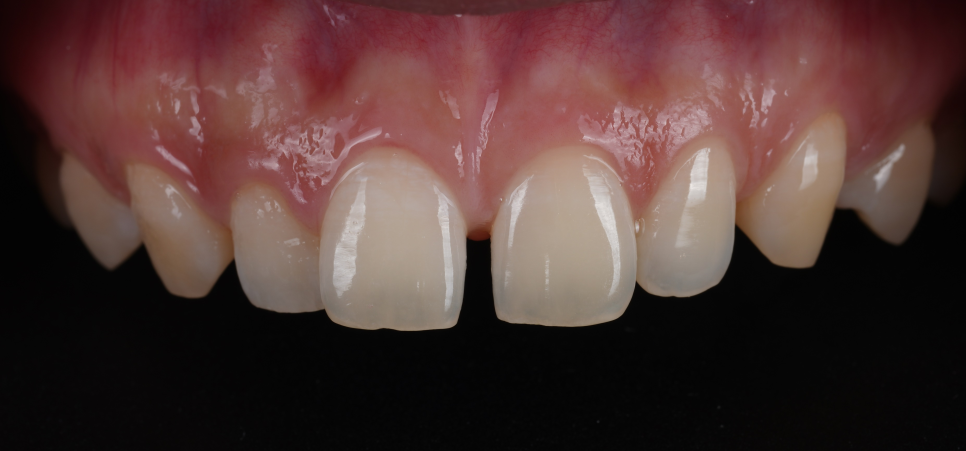

촬영일 : 251121

이 사이만 벌어진 게 아니라 경계 부분에 작은 충치가 발견되어 같이 치료해 드리기로 했어요.

그래서 먼저 앞니 안쪽에 있는 약해진 부분과 충치가 시작된 부분을 깨끗하게 정리하고 내부를 튼튼하게 만들어 줬어요.